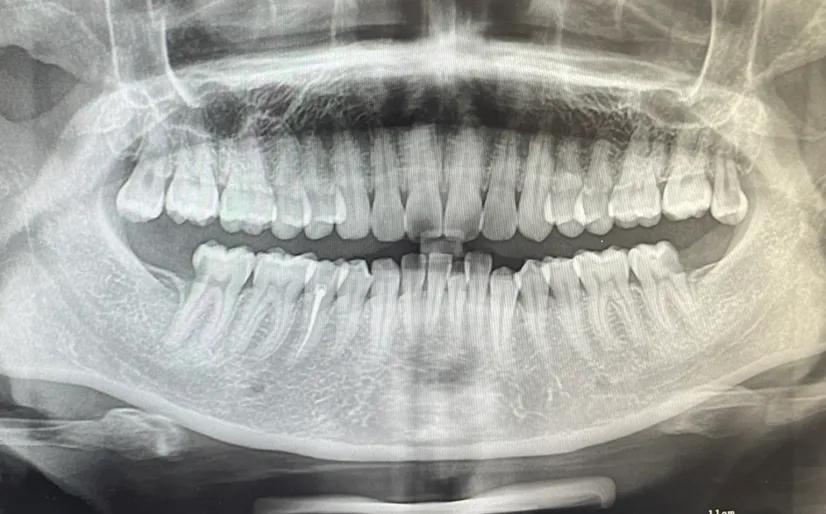

拓展知識:種植牙中間一般要拔多少顆

這個要根據患者的實際情況,不同的患者能承受的不同 。建議到正規(guī)口腔科醫(yī)院【北京三級口腔醫(yī)院】根據患者的情況在決定。患者可以在恢復牙齒咀嚼功能的前提下兼顧牙齒美觀,針對全口牙齒缺失的患者是可以通過全口種植來恢復牙齒功能與美觀的,種牙點擊申領種牙補貼

一般連續(xù)牙齒缺失的情況是可以進行一次種植牙修復的,并且不需要種植多顆種植體,一般需要連續(xù)缺失5顆或者4顆牙,只需要2到3個種植體就足夠,在費用上也省了不少錢,如果有需求一定要選擇正規(guī)專業(yè)點的口腔機構進行缺失牙種植調節(jié)。

一次可以種植2到3顆,但拔牙一次只能拔一顆,等徹底消炎好了才能拔第二顆。

看什么情況才能做決定,正常能做3顆牙左右,特殊情況滿口牙一起種。